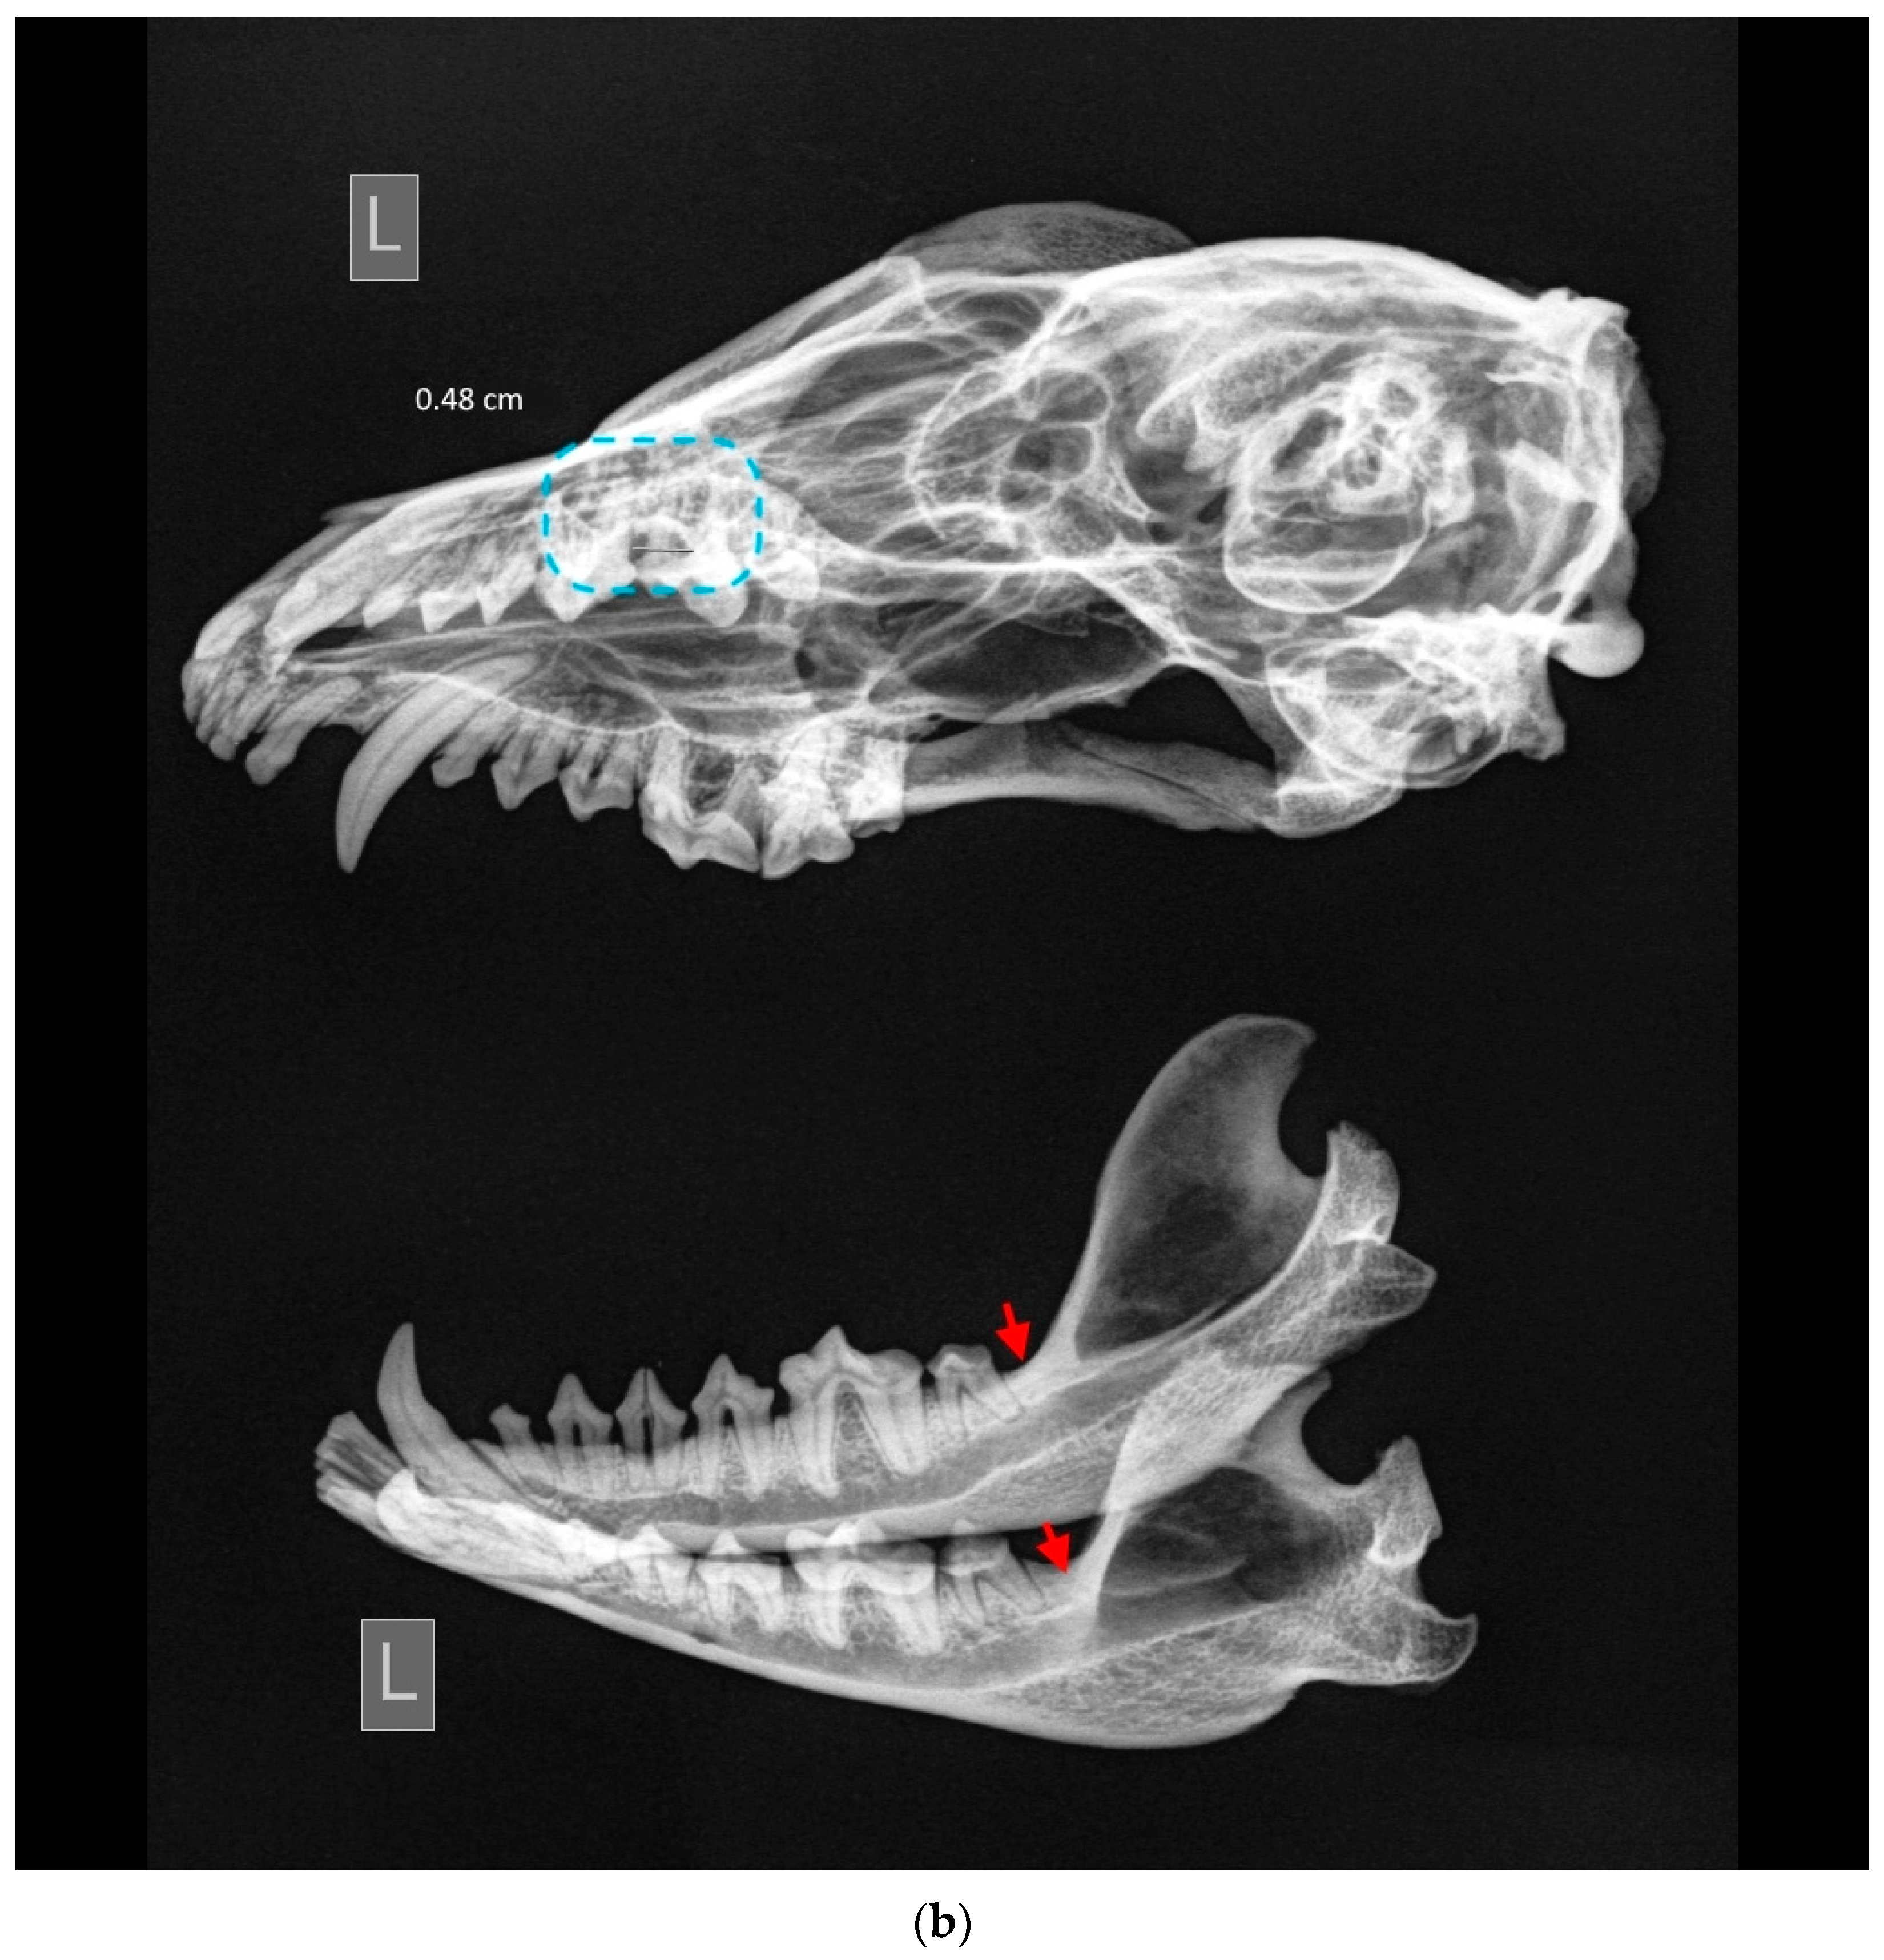

Among observed cases, only one clear instance of stage 4 periodontitis was detected (ID M–0948; Figure 5a,b). The periapical bone resorption had developed around the length of the buccal root of P4. Furthermore, severe periodontitis characterized by significant bone resorption was observed around P3 as well. A milder stage of periodontitis was identified around I3, C, M1, and M1 of the left maxilla.

Figure 5.

ID M–0948, male. (a) Approx. length—120 mm. Fourth-stage periodontitis with local dehiscence (marked by a blue square) of the left mandible and maxilla in the skull of the raccoon dog. (b) X-ray of fourth-stage periodontitis with local dehiscence (marked by a blue square) of the left mandible and maxilla in the skull of a raccoon dog.

In the left mandible, both P3 and P4 exhibited pronounced effects of late-stage periodontitis, with the extent of bone resorption in the periapical area surrounding the roots of these teeth. The molar teeth on the left mandible displayed a comparatively lower degree of periodontitis, yet some loss of surrounding bone was evident.